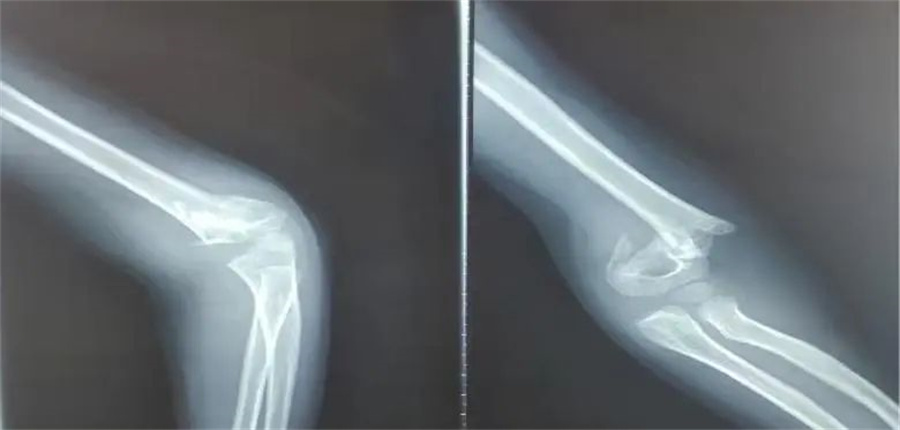

诚瑞的家长赶紧带他来到北京儿童医院集团医院·a片网站 。入院当天,骨科医生发现,孩子是重度伸直型三度肱骨髁上骨折。

在各项检查指标都正常的情况下,儿童医院骨科的医护人员为他做了髁上骨折闭合复位术。

正常情况下,这属于常规手术。但是由于诚瑞太胖,胳膊又短又粗,复位的时候摸不到骨头,无形中增加了手术难度。

骨科医生在放射线下,一点一点摸索,最终复位成功,并且术后没有切口,没有瘢痕,4天后,孩子顺利出院。